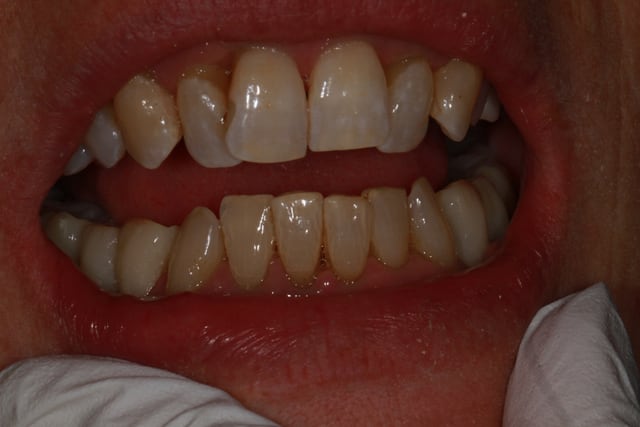

patiente 62 ans région Parisienne, appelle pour un avis, son praticien, paro, imlpanto etc... lui dit que sa paro n'a plus besoin de soin et propose pour les 6 antérieurs (j'ai le devis sous les yeux) 6 Inlay Core et 6 CCM...

Les panos sont du départ, les photos sont après un nettoyage ...profond et soins.